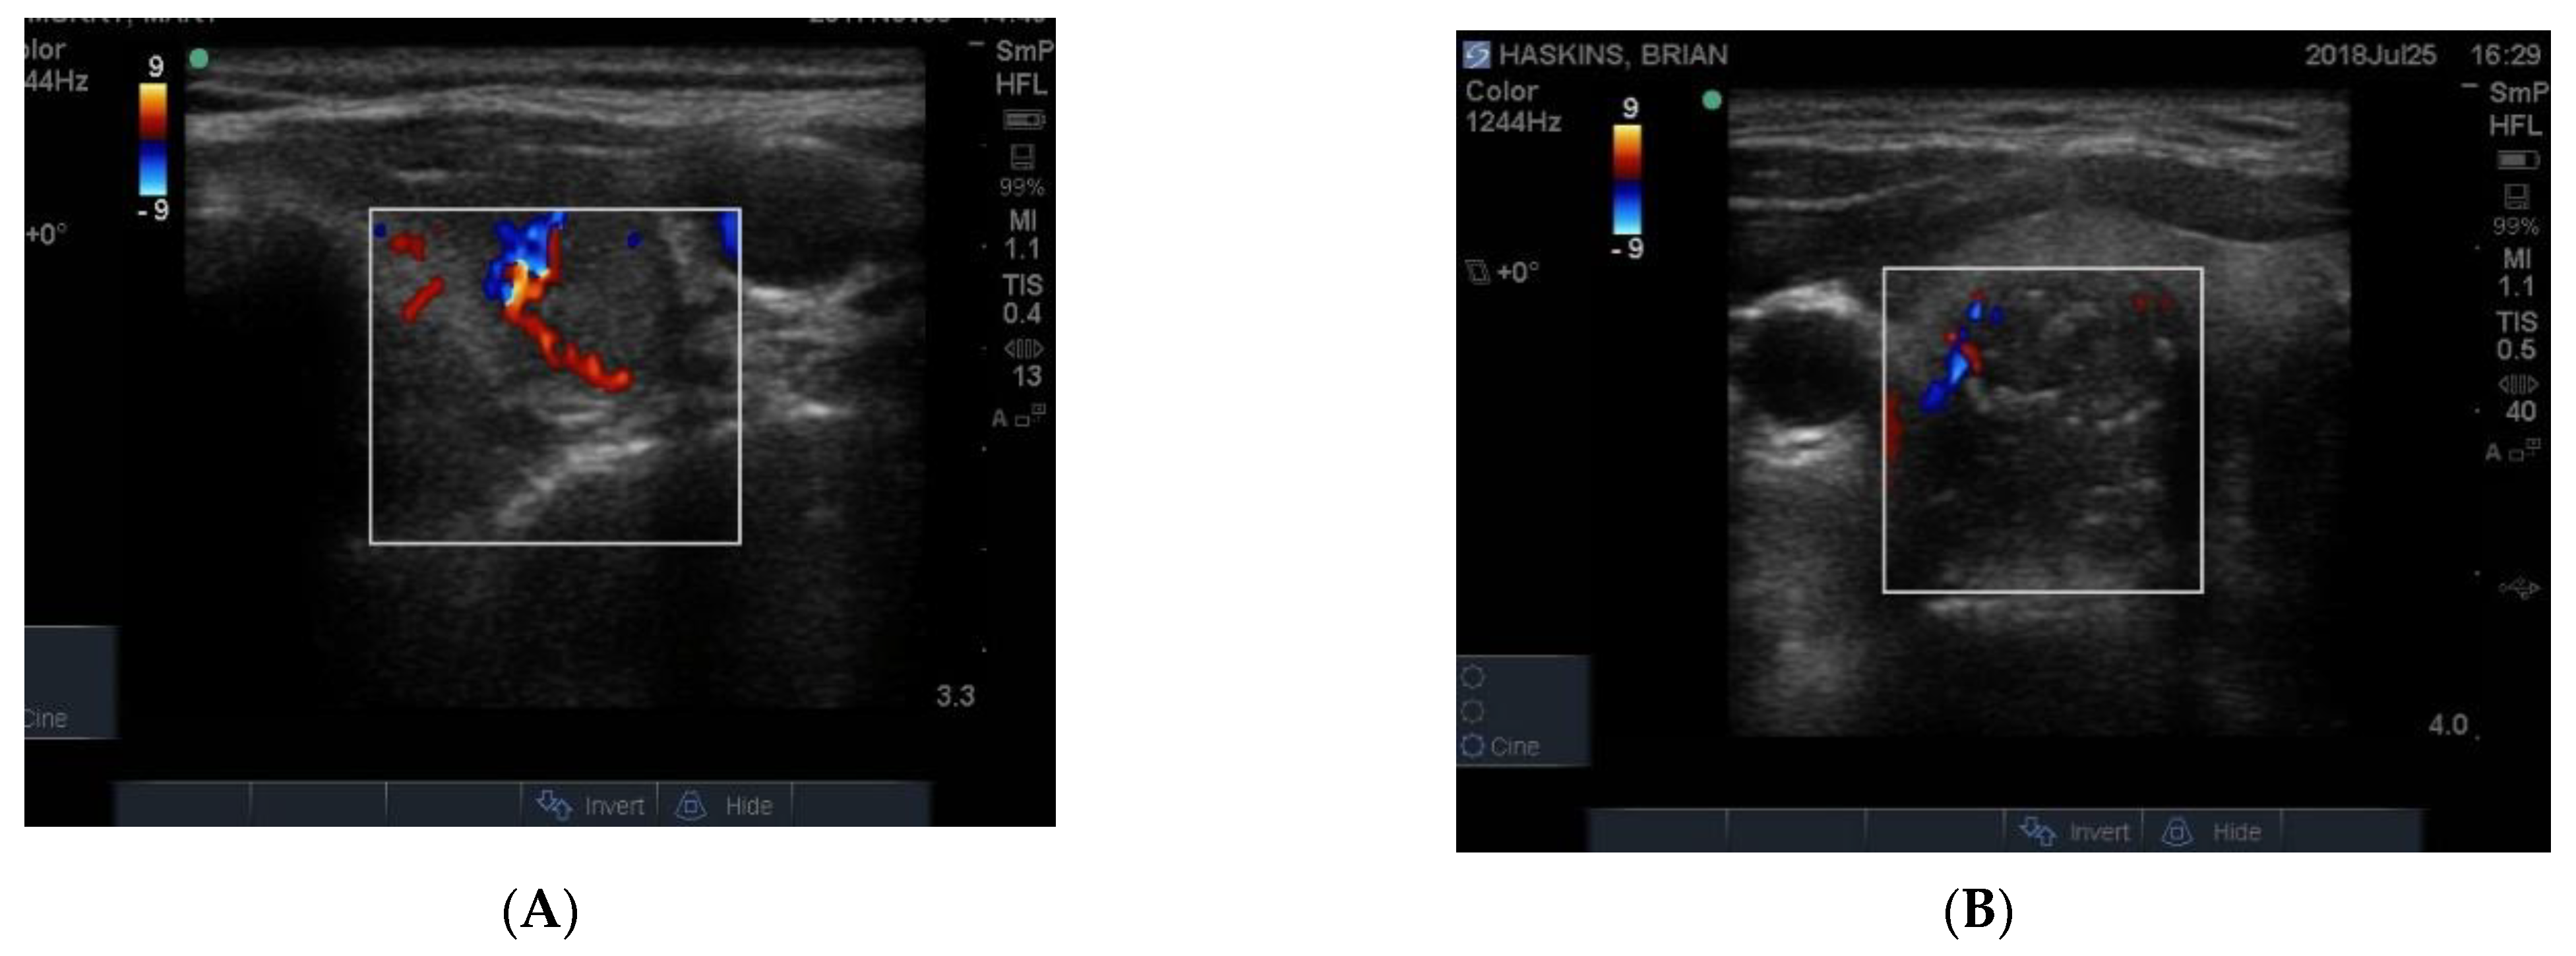

9. Vascularity

The blood supply to thyroid nodules is an important feature to be documented in the course of real time ultrasonography. There are three types of vascularity to be discussed. Firstly, the so-called hypoechoic halo surrounding a benign nodule is caused by compressed blood vessels which can be seen when the “colour” button is engaged. An example of this is seen in Figure 9A. Secondly, the degree of vascularity around the outside of a nodule is reflective of its activity and prominent blood supply around a nodule maybe a sign of thyroid cancer (Figure 9B) [8] but can also be present around nodules shown by biopsy to be benign. It has recently been shown that blood vessels within a nodule, especially if it has other suspicious features (Figure 9B), may be a reliable sign of cancer [9].

Figure 9. Examples of vascularity around the edge of a benign nodule and (A) associated with blotchy macrocalcifications in a hard, irregular edged nodule that is suspicious for papillary cancer (B). Another example of macrocalcifications in papillary thyroid cancer.